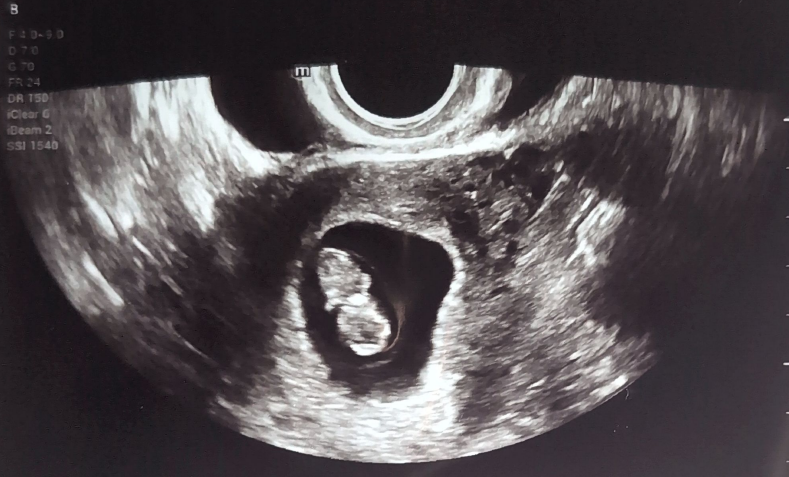

Ultrasound Image

After a few losses, we are so incredibly grateful that this sweet baby is sticking with us. This ultrasound shows her at just 8 weeks — and now we are already 20 weeks and counting. Our little one is growing strong.